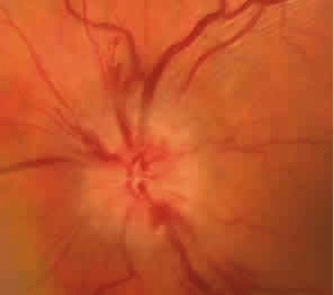

La neuropatía óptica isquémica anterior se manifiesta como una pérdida súbita indolora de la agudeza visual, del campo visual o de ambos. En la pupila del ojo afecto se puede demostrar un defecto pupilar aferente (ver entrada). El fondo de ojo en fase aguda se caracteriza por la presencia de un edema de papila que puede ser parcial (segmentario/sectorial) o generalizado. El edema de papila puede ser pálido o hiperémico. Este hallazgo es necesario para que se considere «anterior» (Figura 1.). Posteriormente el edema de papila evoluciona a una atrofia papilar parcial o generalizada.